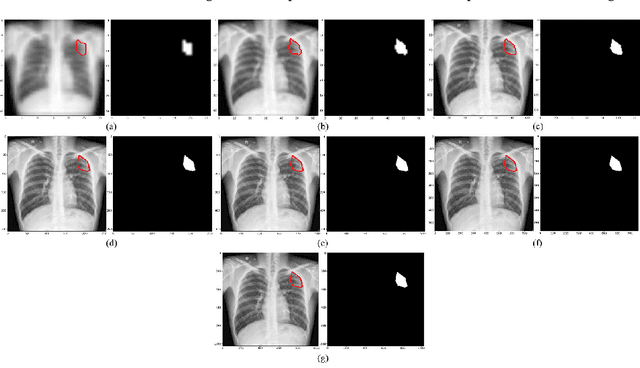

Abstract:Deep learning (DL) has drawn tremendous attention in object localization and recognition for both natural and medical images. U-Net segmentation models have demonstrated superior performance compared to conventional hand-crafted feature-based methods. Medical image modality-specific DL models are better at transferring domain knowledge to a relevant target task than those that are pretrained on stock photography images. This helps improve model adaptation, generalization, and class-specific region of interest (ROI) localization. In this study, we train chest X-ray (CXR) modality-specific U-Nets and other state-of-the-art U-Net models for semantic segmentation of tuberculosis (TB)-consistent findings. Automated segmentation of such manifestations could help radiologists reduce errors and supplement decision-making while improving patient care and productivity. Our approach uses the publicly available TBX11K CXR dataset with weak TB annotations, typically provided as bounding boxes, to train a set of U-Net models. Next, we improve the results by augmenting the training data with weak localizations, post-processed into an ROI mask, from a DL classifier that is trained to classify CXRs as showing normal lungs or suspected TB manifestations. Test data are individually derived from the TBX11K CXR training distribution and other cross-institutional collections including the Shenzhen TB and Montgomery TB CXR datasets. We observe that our augmented training strategy helped the CXR modality-specific U-Net models achieve superior performance with test data derived from the TBX11K CXR training distribution as well as from cross-institutional collections (p < 0.05).